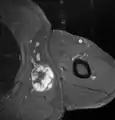

Medical ultrasonography and magnetic resonance imaging (MRI) of liposarcomas are helpful and often essential in determining their extent, surgical accessibility, and relationship to any observed organ dysfunctions. Since ultrasonography is usually unable to distinguish a liposarcoma from a benign lipoma, MRI is the initial imaging of choice to provide evidence relative to making this distinction.[67]

In myxoid liposarcoma, it shows low signal intensity mass with high signal intensity foci on T1-weighted MRI images. The mass shows high signal intensity on T2-weighted images. This is because it contains predominantly mucoid substance (accounts for low signal intensity on T1) and small amount of mature fat (accounts for high signal intensity on T1).[68] The mass is well-defined, lobulated, multiloculated, or oval in shape without any infiltration into surrounding structures.[68]